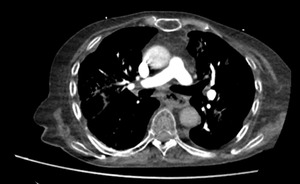

Three days after hospitalization, the patient developed an altered level of consciousness along with symptoms of polypnea (28 breaths/min), oxygen saturation of 87% on room air, tachycardia at 155 beats/min, and hypotension (85/55 mmHg). Tympanic temperature was 36.6°C. On examination, she appeared cachectic. Capillary refill time was over 3 seconds, and jugular venous distension was noted, but heart and respiratory sounds were unremarkable. The abdomen was soft and non-tender, with no organomegaly. Neurological examination revealed reduced muscle strength in both lower limbs and cognitive impairment. Hemodynamic monitoring indicated cardiogenic shock, and resuscitation was initiated immediately. Given her clinical presentation, a pulmonary embolism was initially suspected. However, a contrast-enhanced chest CT scan ruled out a pulmonary embolism.